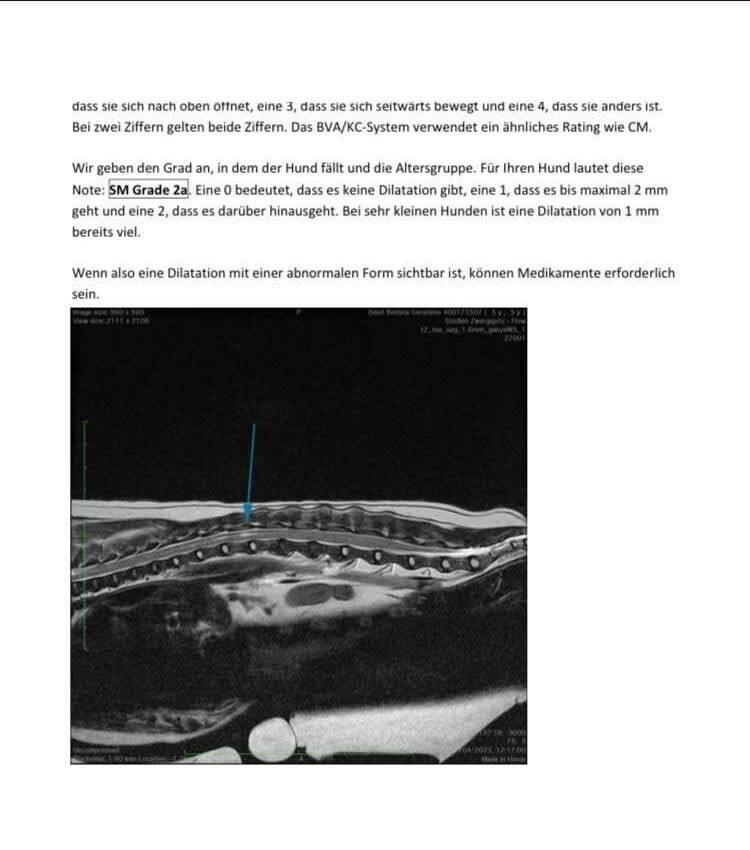

Und als Bild hänge ich noch den Befund von dem Neurologen an betreffend SM und CM.

Dazu kommt noch seine Syringomelie Grad 2 und

Chiari Malformation Grad 1.